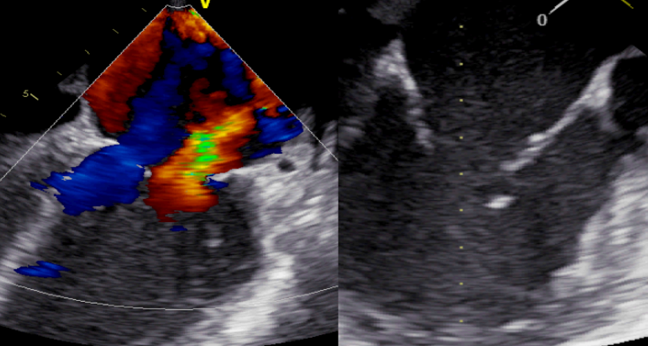

For patients with acute mitral regurgitation (MR) following myocardial infarction, including those who present with and without cardiogenic shock, treatment with MitraClip (Abbott) may be a viable option for this high-risk cohort who have no surgical alternative, according to a small, retrospective series.

Presenting the IREMMI results during today’s  late-breaking clinical science session at TCT Connect 2020, Rodrigo Estévez-Loureiro, MD, PhD (University Hospital Alvaro Cunqueiro, Vigo, Spain), explained that MR stemming from papillary muscle rupture was infrequent in their series, with most of it due to acute ventricular remodeling and restriction of the posterior mitral leaflet.

At baseline, 86% and 79% of shock and nonshock patients had MR grade 4. Immediately after MitraClip implantation, the majority of patients had a significant improvement in MR grade, with more than 60% getting to an MR grade of 0-1. These benefits were observed in shock and nonshock patients. At 3 months, the results were similar, with again no difference in MR improvement seen between shock and nonshock patients treated with MitraClip. NYHA functional class was also improved: while the majority were in NYHA class IV at baseline, 80% and 85% of the cardiogenic shock and noncardiogenic shock patients, respectively, were in NYHA class I or II at follow-up (P = 0.608 for difference between groups).